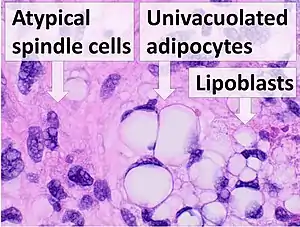

| Histopathology of liposarcoma, H&E stain:[1] - | |

All liposarcomas consist of at least some cells that bear a resemblance to fat cells when examined for their histopathologic appearances under a microscope.[4] However, the liposarcomas do have several forms based on differences in their clinical presentations (e.g. ages, gender preferences, sites of tumors, signs, and symptoms), severities (i.e. potential to invade local tissues, recur after surgical removal, and metastasize to distal tissues), genetic abnormalities, prognoses, and preferred treatment regimens. The World Health Organization in 2020 reclassified liposarcomas into five more or less distinct forms: 1) atypical lipomatous tumor/well-differentiated liposarcoma (WD-LPS); 2) dedifferentiated liposarcoma (DD-LPS); 3) myxoid liposarcoma; 4) pleomorphic liposarcoma; and 5) myxoid pleomorphic liposarcoma.[5] (Pleomorphic indicates the presence of cells that have abnormal and often large variations in their size and shape and/or the size and shape of their nuclei.)

Histopathologically, ALT/WDL tumors are divided into adipocytic/lipoma-like, sclerosing, and inflammatory variants with adipocyte/lipoma-like being the most common. Adipocytic/lipoma-like ALT/WDL tumors consist of lobules of mature fat cells variably intersected with irregular fibrous septa (see the adjacent H&E stained photomicrograph). Sclerosing ALT/WDL tumors, the second most common variant, develop primarily in the retroperitoneal and paratesticular areas; it consists of scattered, atypical stromal cells within a collagenous (i.e. collagen-containing) stromal tissue background. Rare vacuole-containing lipoblasts populate this tissue. Inflammatory ALT/WDL tumors are the rarest variant. they occur most frequently in the retroperitoneum and consists of chronic inflammatory cells, e.g. lymphocytes and plasma cells plus occasional lymph node-like follicles interspersed throughout a tissue background containing fat cells.[14]